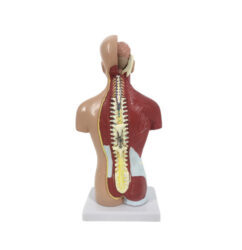

ATL-11 MALE MUSCLES FIGURE INTERNAL ORGANS HARD

The model is an anatomically accurate representation of the human anatomy, complete with superficial and deep musculature, the digestive system, lymphatic system, respiratory system, urinary system, circulatory system, endocrine system, and nervous system. Our model has removable organs and dissectible features for a complete educational experience.

Classification: